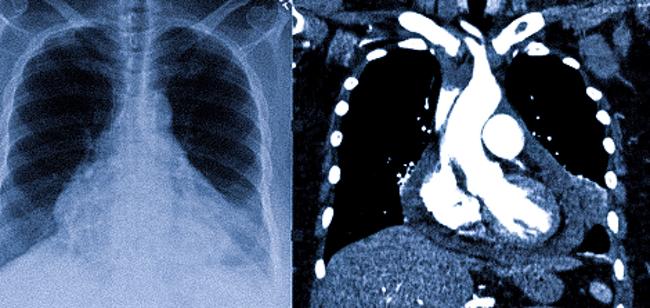

На КТ сердце увеличено что это значит

С помощью рентгенографии (слева) органов грудной клетки (ОГК) и КТ с контрастированием (справа) возможно визуализация сердца и крупных сосудов

В большинстве случаев компьютерная томография не является предпочтительным вариантом для диагностики заболеваний сердца. Эхокардиография занимает эту нишу, так как она более доступна, проста и информативна. С помощью Эхо-КГ врач может оценить не только анатомию сердца, но и его функциональность (например, скорость и объем кровотока, наличие регургитации через клапаны).

Что касается врожденных аномалий, компьютерная томография может быть полезна, так как отличается высокой чувствительностью к патологиям крупных сосудов. Визуализация изменений в сердце возможно лишь при наличии выраженных отклонений.

Специалисты предпринимают попытки внедрить КТ-сканирование, синхронизированное с электрокардиографией, что потенциально способно значительно повысить эффективность данного метода инструментальной диагностики. Результаты описанных исследований свидетельствуют о перспективности последнего. Ограничивающим фактором является молодой возраст пациента, при котором нежелательно излишнее лучевое воздействие на организм. Поэтому при необходимости диагностики пороков сердца, предпочтение обычно отдают Эхо-КГ и МРТ.

Стандартная компьютерная томография имеет большое значение в качестве дополнительного метода исследования или когда у пациентов установлен электронный кардиостимулятор, либо имеются другие противопоказания для магнитно-резонансной томографии (присутствие металлических элементов, несъемные устройства, которые могут выйти из строя под влиянием магнитного поля).